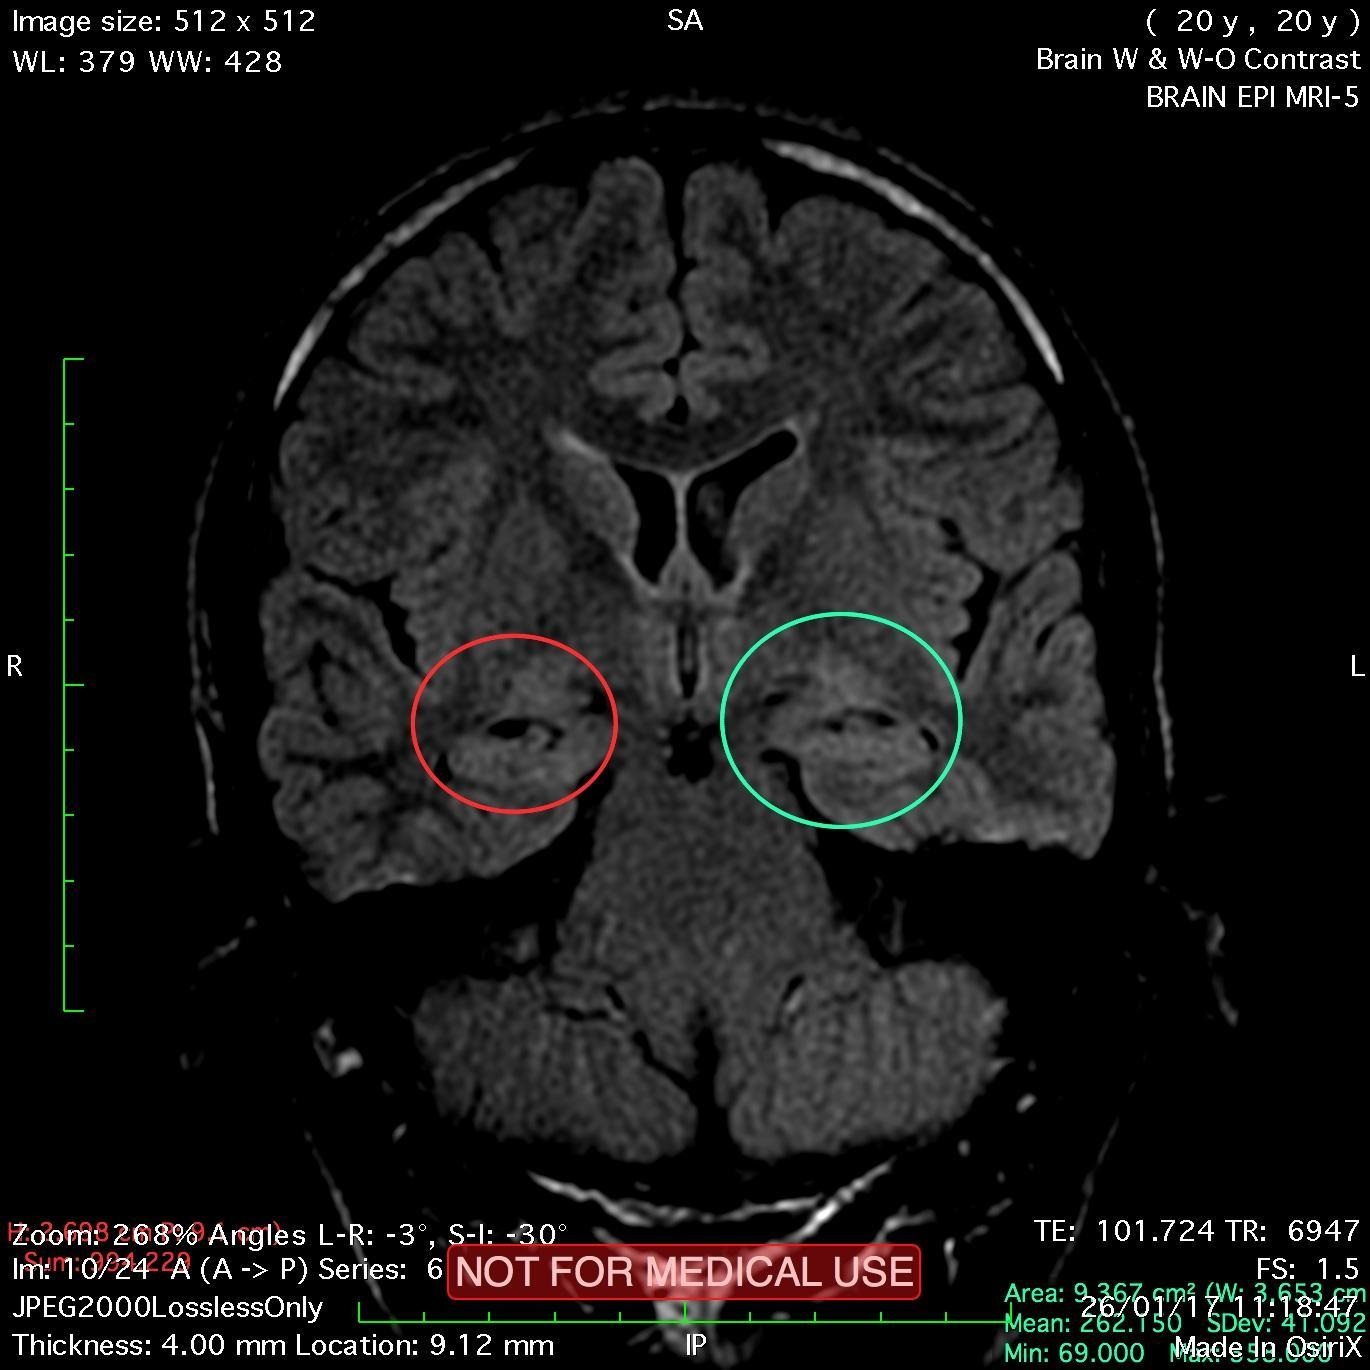

Secondary hippocampal sclerosis is identified, bilaterally (secondary to long-term intractable epilepsy).